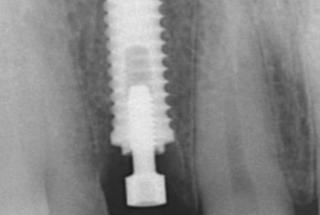

Clinical cases

MPI closely monitors clinical cases in the market to ensure their correct functioning and successful outcome.